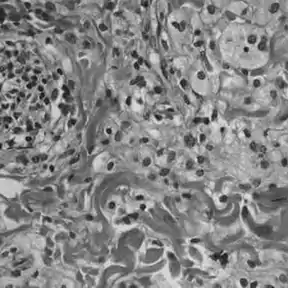

Histologically, ECD differs from Langerhans cell histiocytosis (LCH) in a number of ways. Unlike LCH, ECD does not stain positive for S-100 proteins or Group 1 CD1a glycoproteins, and electron microscopy of cell cytoplasm does not disclose Birbeck granules.[6] Tissue samples show xanthomatous or xanthogranulomatous infiltration by lipid-laden or foamy histiocytes, and are usually surrounded by fibrosis. Bone biopsy is said to offer the greatest likelihood of reaching a diagnosis. It would appear that approximately half these patients harbor point mutations of the BRAF gene at codon 600 substituting the amino acid glutamine for valine. In some, there is histiocyte proliferation, and on staining, the section is CD68+ and CD1a-.